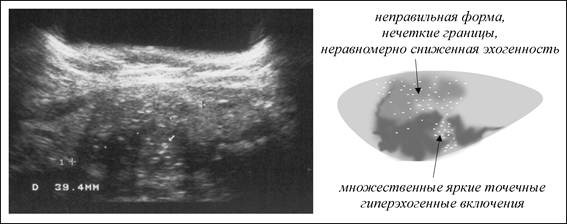

Гиперэхогенность почек возникает, когда эти парные органы претерпевают изменения в форме, структуре или размере под воздействием различных факторов. Обычно это связано с нарушениями обмена веществ, травмами или неконтролируемым ростом тканей в отдельных областях. Образования, которые вызывают сильное отражение ультразвука, чаще всего формируются в паренхиме и почечных пирамидах, и могут проявляться на экране в виде белых точек и пятен разных размеров.

Для получения полного представления о состоянии почек обязательно проводится ультразвуковое исследование. Специалист сможет легко выявить наличие гиперэхогенных включений и оценить состояние паренхимы на фоне выделяющихся пирамид.

Одной из форм патологий почечных пирамид является синдром перимедуллярного кольца. На экране при ультразвуковом исследовании можно увидеть белые кольцевидные пятна. Это состояние возникает из-за фиброзных образований и кальцификации сосочков пирамид, что может быть следствием эндокринных заболеваний (таких как сахарный диабет и нарушения работы паращитовидных желез), пиелонефрита и ряда других заболеваний. Некоторые специалисты рассматривают данное состояние не как отдельное заболевание, а как этап развития синдрома выделяющихся пирамидок.